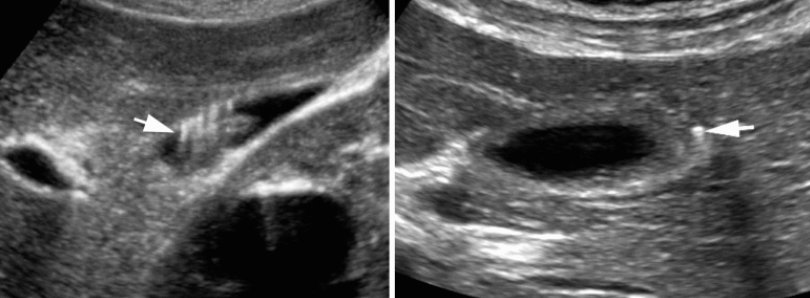

US finding

- 소낭종 (anechoic)

- 소낭종내담석에 의한 comet tail sign

- GB wall 이 두꺼워진다

- 미세낭종의 벽에 부딪혀 다중반사를 형성 (comet-tail artifact )